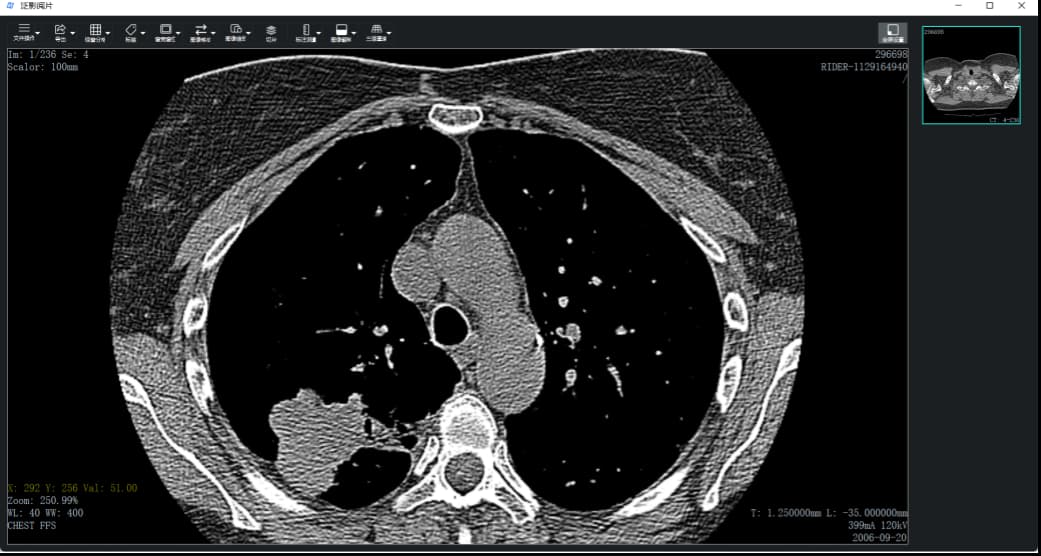

如下图为关闭注释后的效果。

单击工具栏上的“标签”按钮或按”Shift+F12”键可以关闭和打开注释。